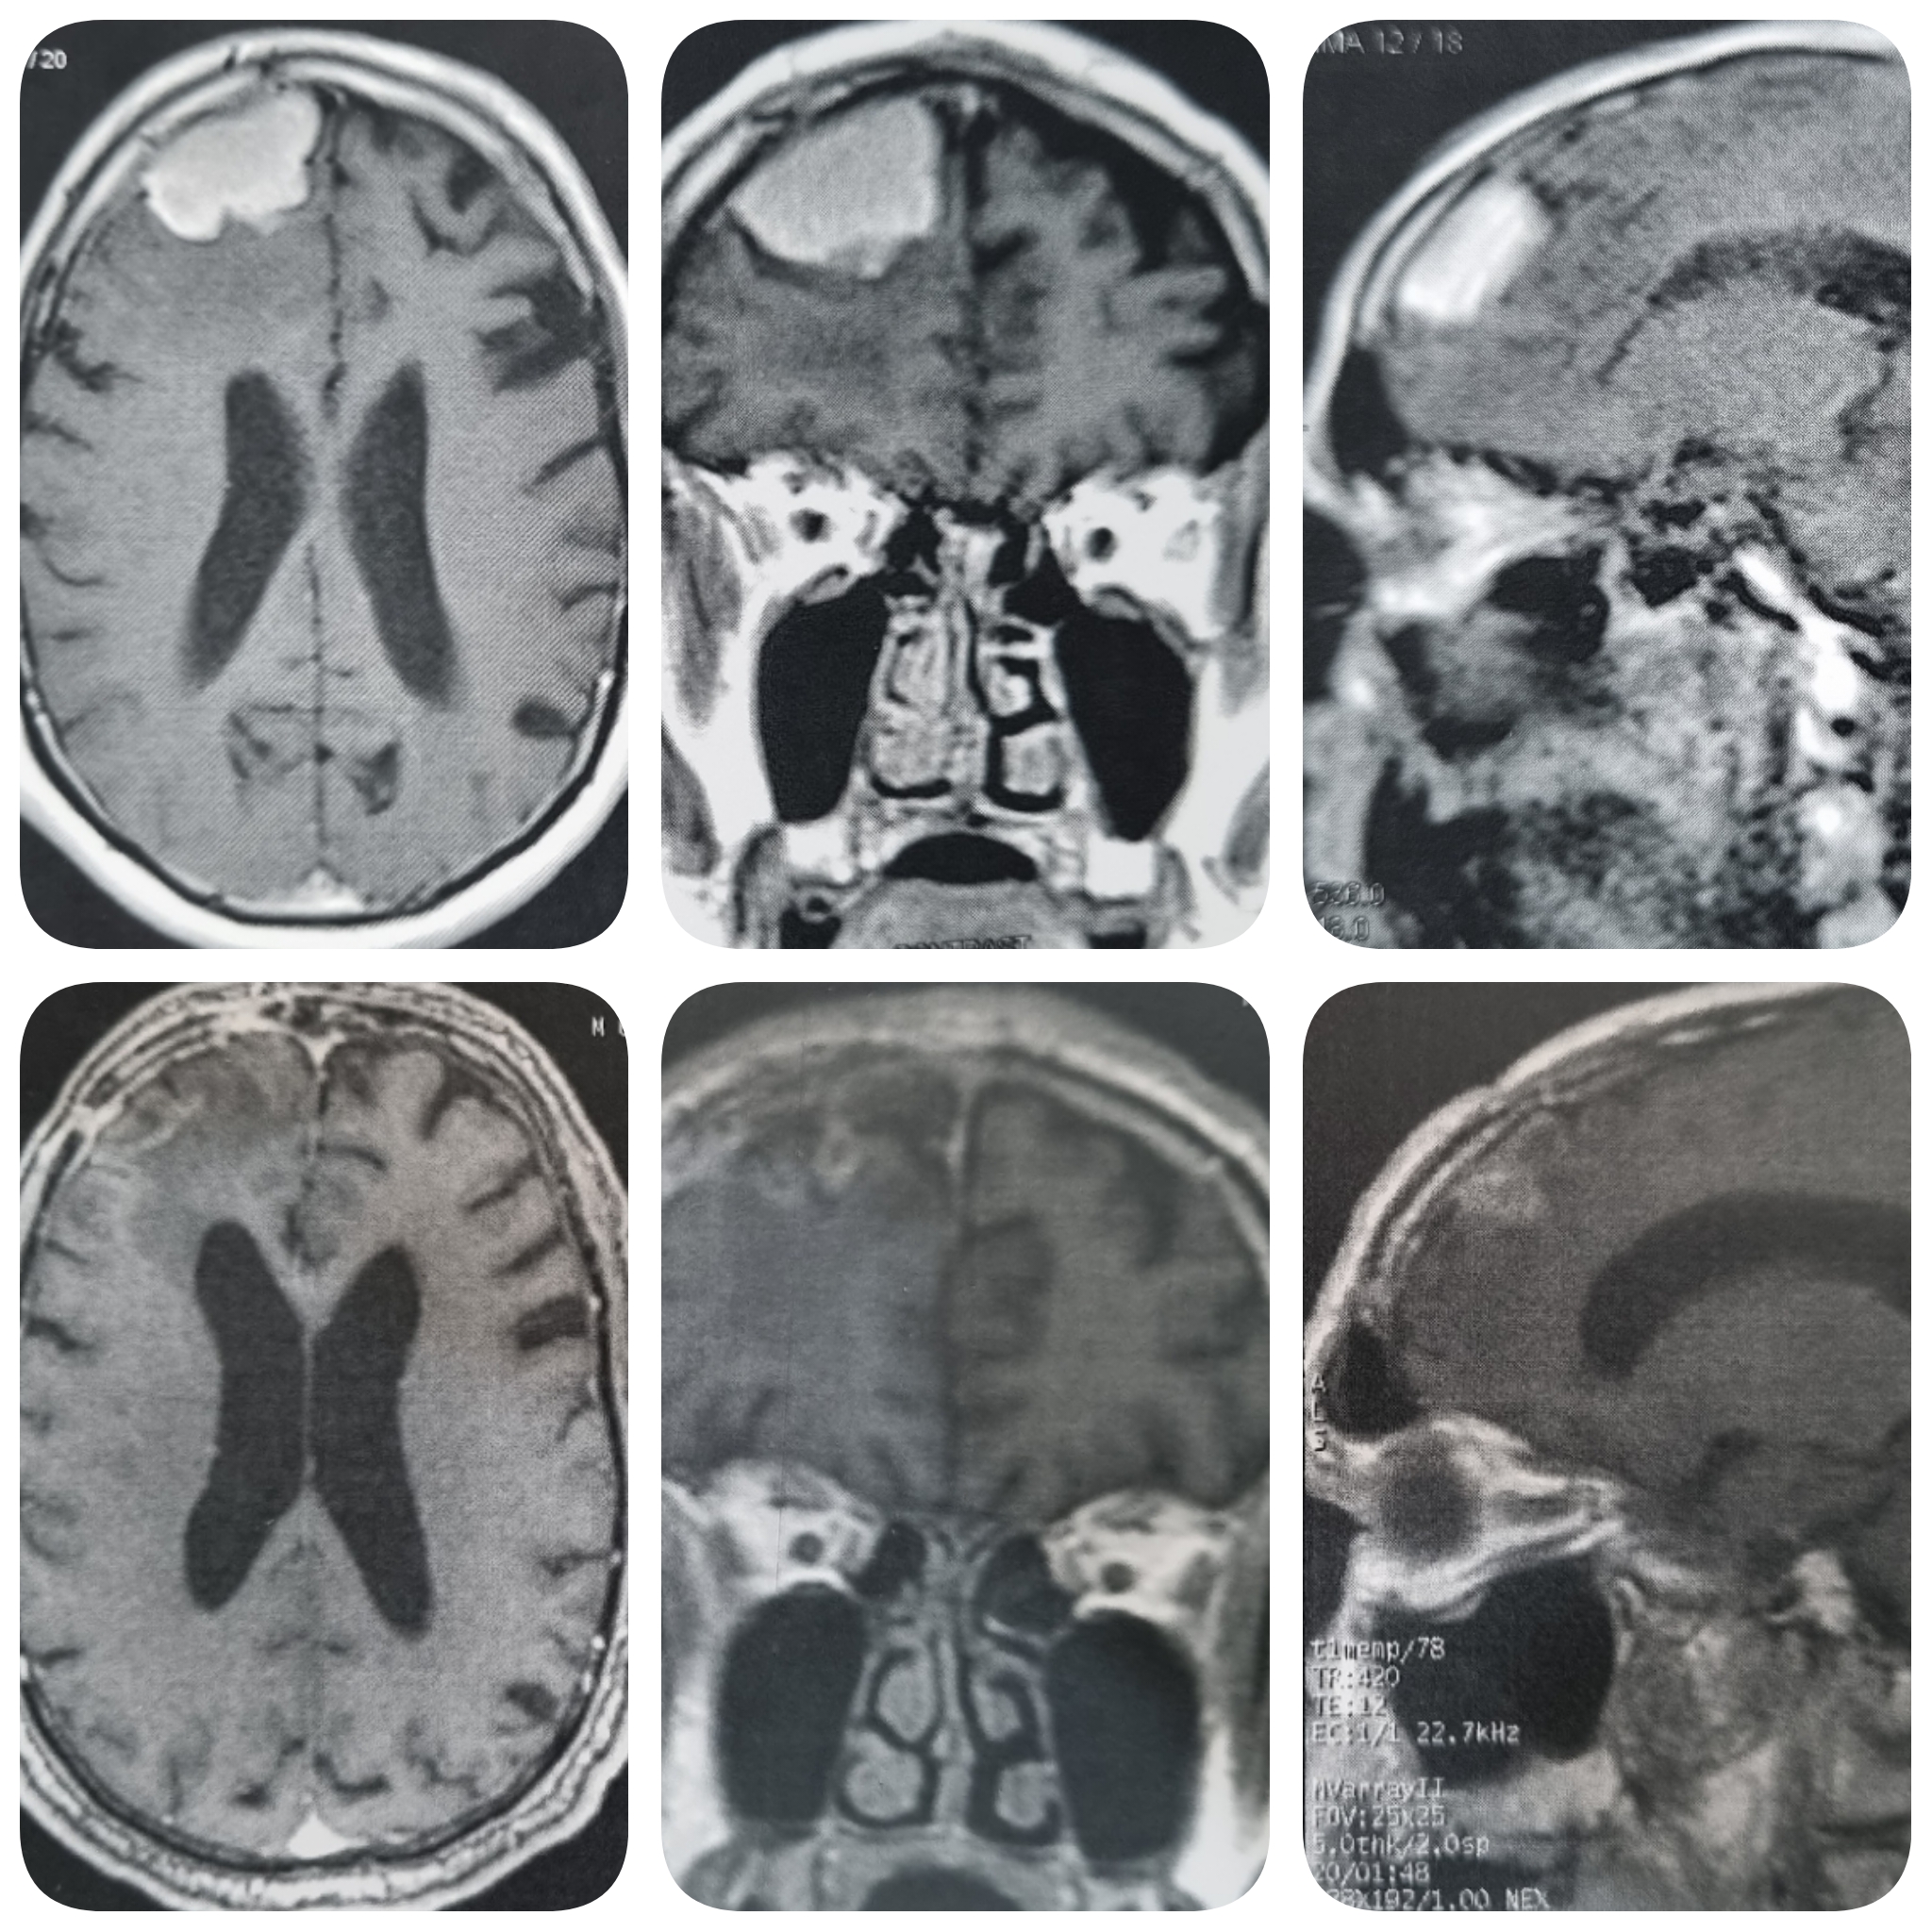

– الرنين المغناطيسي على المخ بالصبغة، والذي يظهر مكان الورم، ويساعد في التخطيط للجراحة.

2- الجراحة لاستئصال الورم، وأحياناً نلجأ لاستئصال الورم مع الجزء من عظام الجمجمة المحيط به واستبدالها ببديل صناعي.

أمثلة لاستئصال أورام أغشية المخ الحميدة بالجراحة الميكروسكوبية